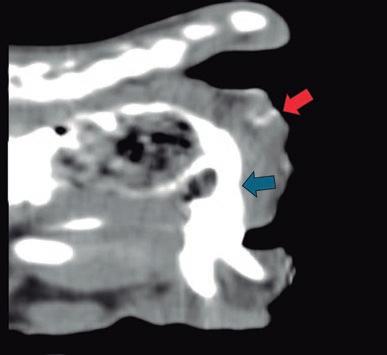

La radiología intervencionista, también conocida como radiología vascular e intervencionista, es una especialidad que se encarga del diagnóstico y tratamiento de una gran cantidad de enfermedades de una manera mínimamente invasiva. Se realiza mediante un abordaje guiado por distintas técnicas de imagen como, por ejemplo, la ecografía, la fluoroscopia o la tomografía computarizada, para alcanzar la zona a diagnosticar o tratar.

imágenes basadas en rayos X y posteriormente las convierte en una señal de vídeo en tiempo real. Estas imágenes pueden manipularse ofreciendo funciones como la angiografía de sustracción digital, mapeo vascular y ampliación. Respecto a una radiografía, la exposición de rayos X necesaria para realizar una fluoroscopia es baja, pero debido a la duración de las series de imágenes que habitualmente se toman, el nivel de exposición en los pacientes suele ser elevado. Por lo tanto, es importante controlar el tiempo de exposición y llevar un registro de este. El fluoroscopio debe estar situado en una sala adecuada para su uso seguro, y todo el personal que entre en la sala de fluoroscopia debe protegerse de la radiación utilizando un delantal plomado, protectores de tiroides y gafas plomadas.